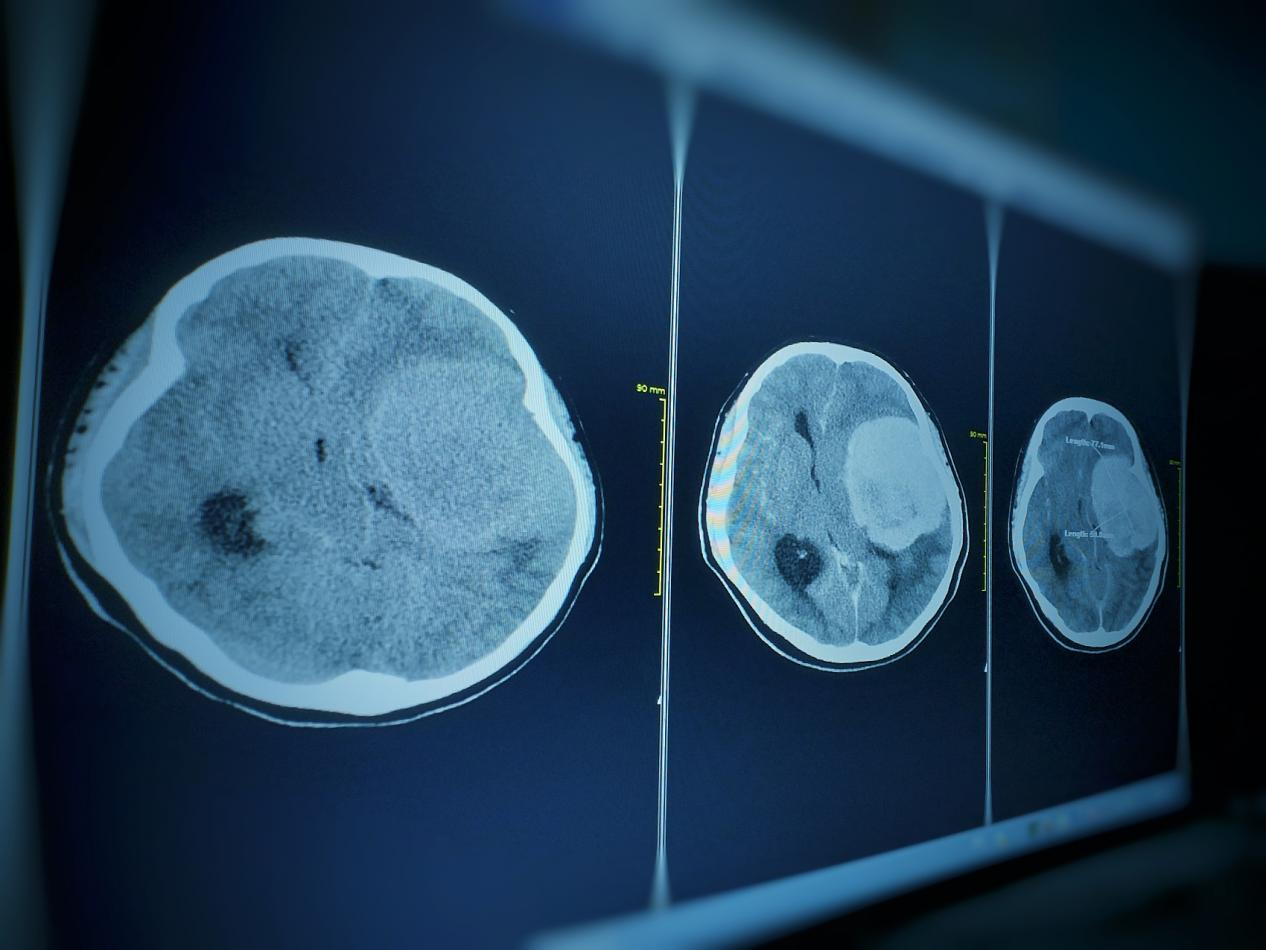

脑膜瘤放射治疗医院,昆明脑膜瘤医院哪家好-昆明医科肿瘤医院脑膜瘤是一种生长在脑膜上的肿瘤,它可能是恶性的也可能是良性的。对于一些较大或难以手术的脑膜瘤,放射治疗可能是一种有效的治疗方法。本文将介绍脑膜瘤放射治疗的原理、过程、风险和预后。脑膜瘤放射治疗的原理脑膜...

脑膜瘤的临床表现,昆明脑膜瘤医院哪家好-昆明医科肿瘤医院脑膜瘤是一种常见的颅内肿瘤,它通常发生在脑膜(覆盖脑部和脊髓的薄膜)上。由于它的位置和生长速度不同,其症状和表现也会因个体差异而有所不同。但是,一些常见的症状和诊断方法可以帮助医生和患者及时发现和治疗脑膜...

昆明脑膜瘤放射治方法,昆明脑膜瘤医院哪家好-昆明医科肿瘤医院脑膜瘤是一种危险的脑部肿瘤,治疗需要综合考虑患者的个体情况和病情,通常需要多种治疗方法的组合应用。以下是昆明治疗脑膜瘤的一些常用方法:手术切除手术切除是治疗脑膜瘤的首选方法。手术可以通过开颅手术或经鼻...

昆明脑膜瘤放射治疗方式,昆明脑膜瘤医院哪家好-昆明医科肿瘤医院脑膜瘤(Meningiomas)是起源于脑膜及脑膜间隙的衍生物,发病率占颅内肿瘤的19.2%,居第2位,女性:男性为2:1,发病高峰年龄在45岁,儿童少见。许多无症状脑膜瘤多为偶然发现。脑膜瘤是指发...

脑膜瘤放射治疗医院,昆明脑膜瘤医院哪家好-昆明医科肿瘤医院脑膜瘤是一种发生在脑膜(脑部外层覆盖的薄膜)上的肿瘤。它通常是良性的,但在某些情况下也可能是恶性的。脑膜瘤的治疗通常需要一个综合治疗方案,其中包括手术切除、放射治疗和化疗。放射治疗是一种常用的治疗方法,...